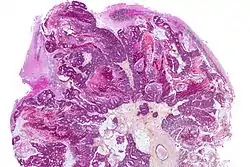

نقيلة الدماغ (بالإنجليزية: Brain metastasis) هي نوع من أنواع انتشار الأورام الخبيثة والذي ينتج من انتشار الورم السرطاني من جزء مصاب به وانتقاله إلى الدماغ.[1]